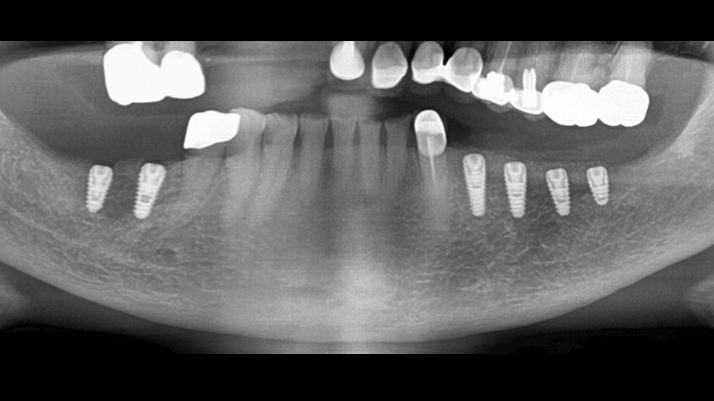

Clinical case: Ridge splitting technique using SmarThor + AnyRidge as expander

- Courtesy of Dr.Kwang-Bum Park, Korea -

Keywords

AnyRidge, ridge splitting, GBR, Dr. Kwang-Bum Park, mandibular posterior, SmartThor, Mega-Oss, thin ridge, bone regeneration

Products:

AnyRidge implant system. SmarThor, Mega-Oss

“Thin ridge expansion with minimally invasive surgery!

Use SmarThor & AnyRidge to place a wider diameter implant with minimal drilling after ridge splitting, even in thin ridge under 2mm! “